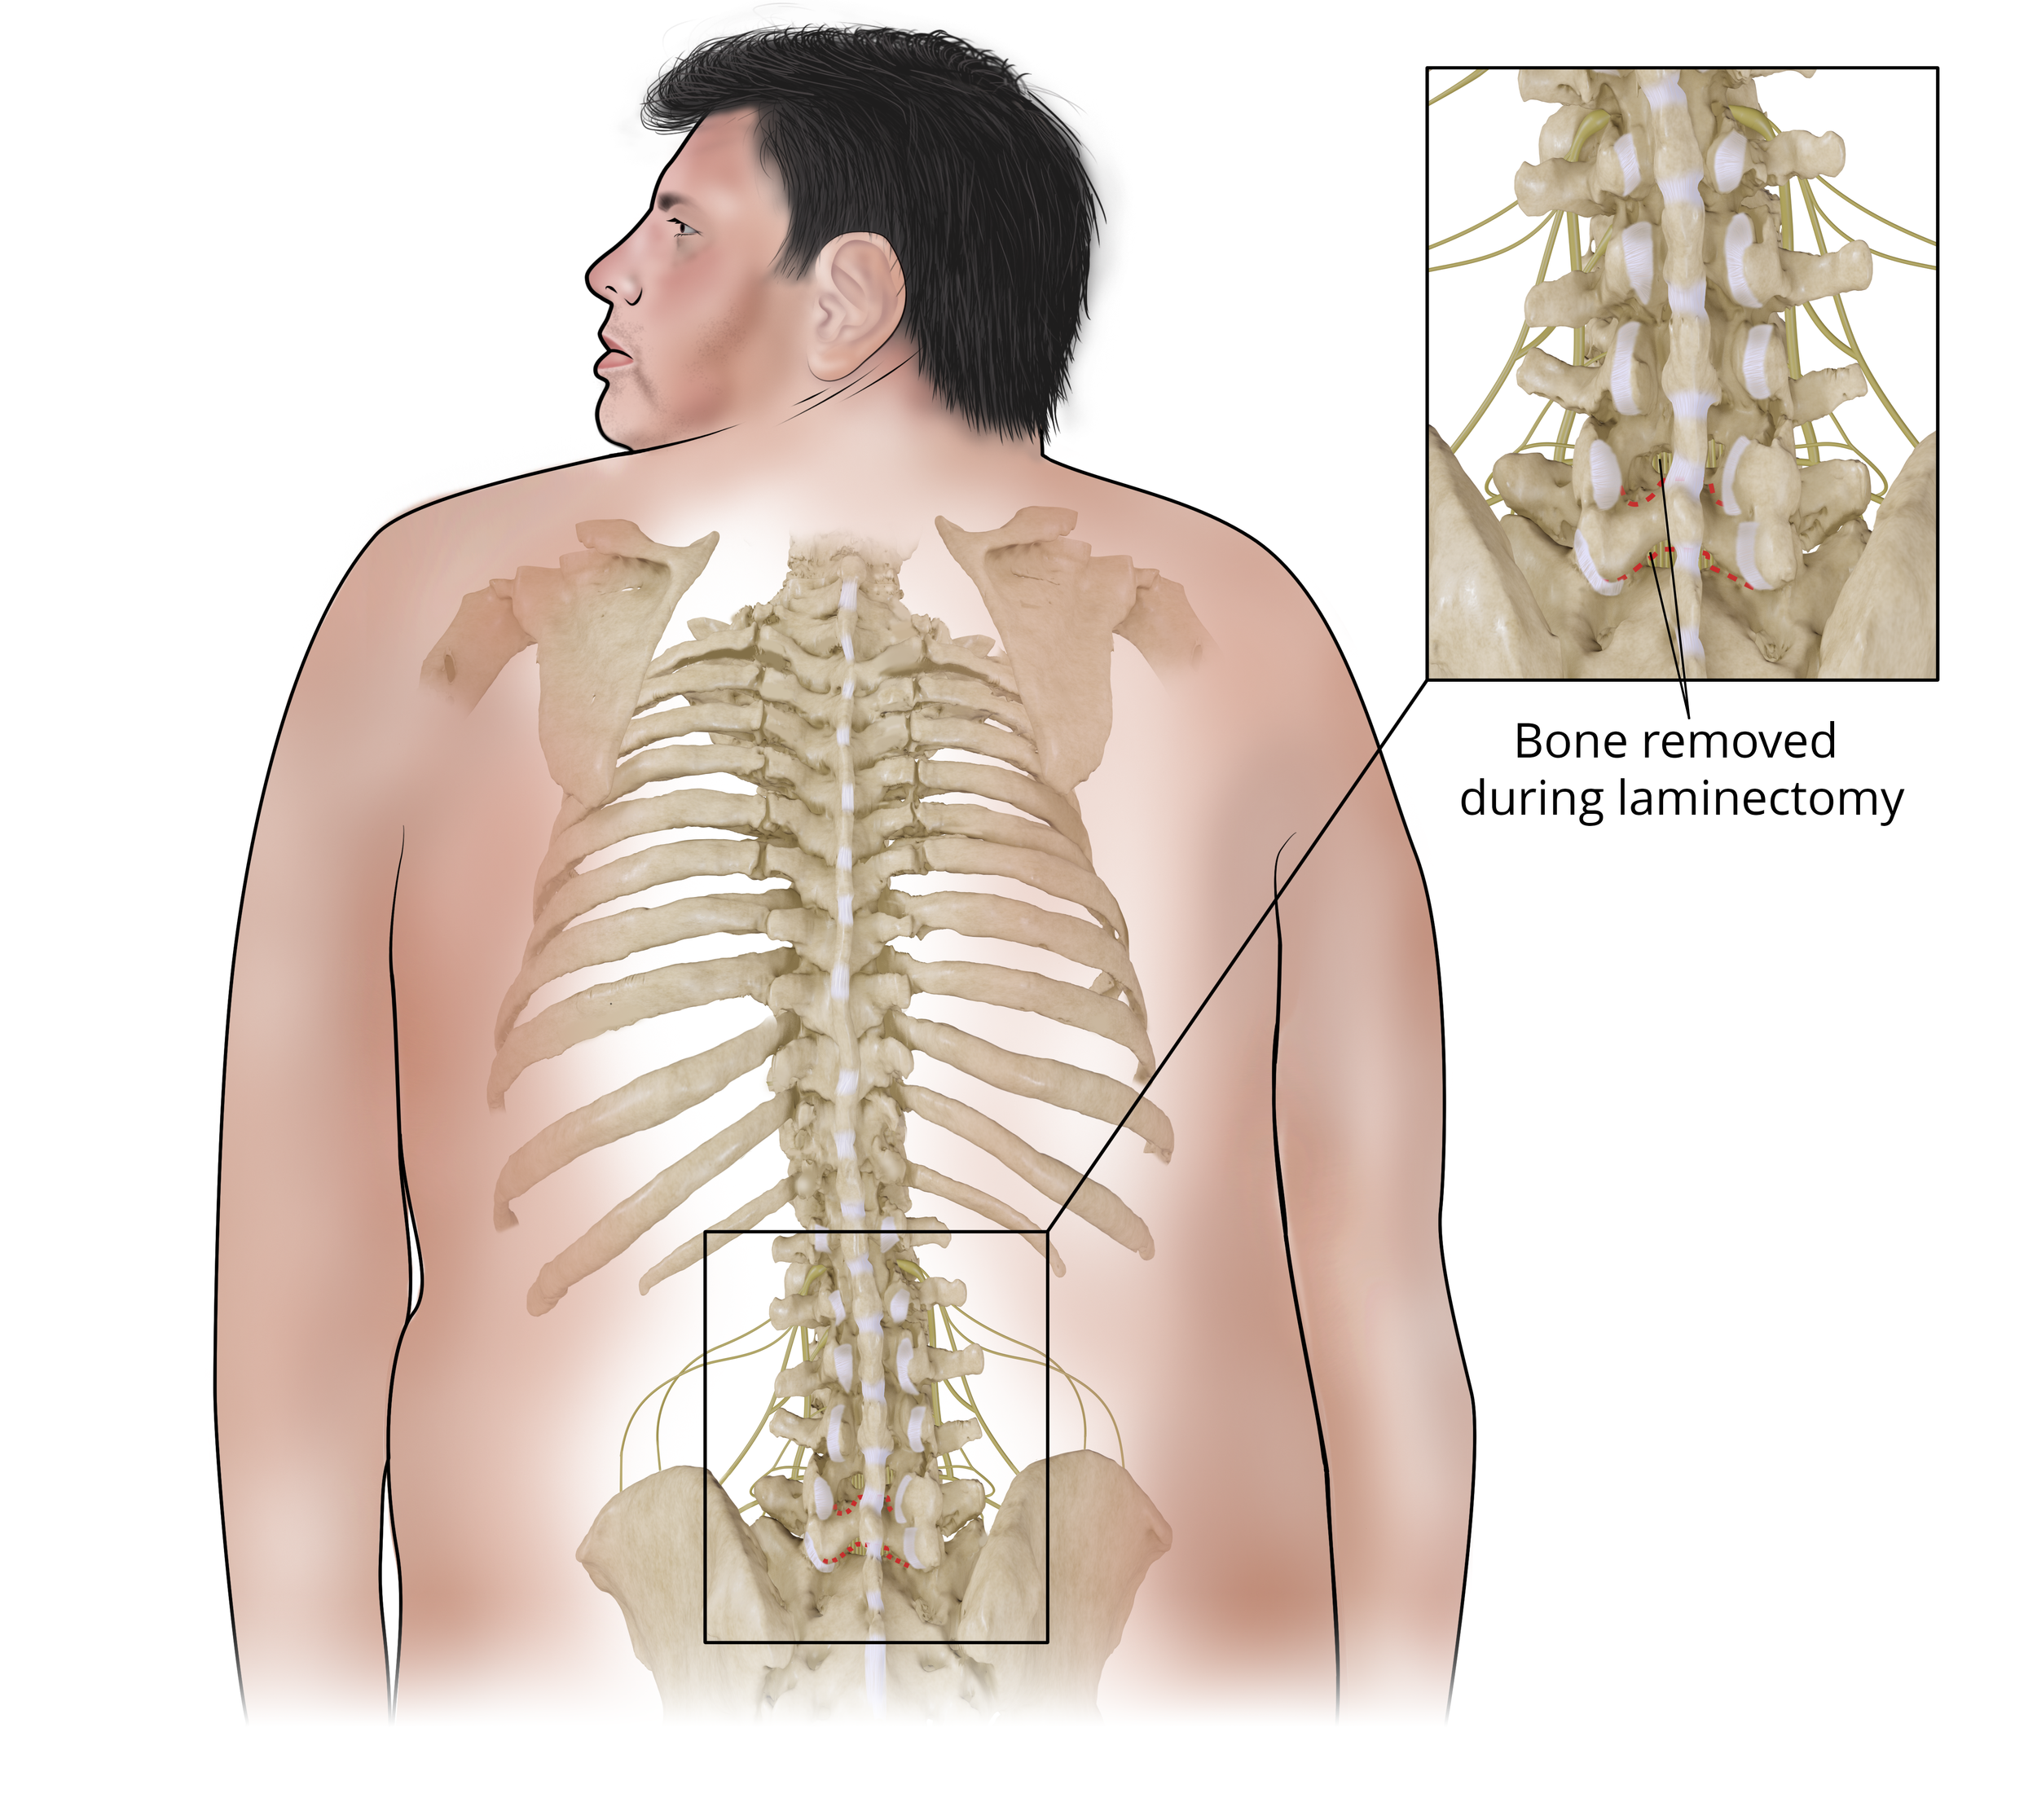

Healed Transverse Processes and Laminectomy